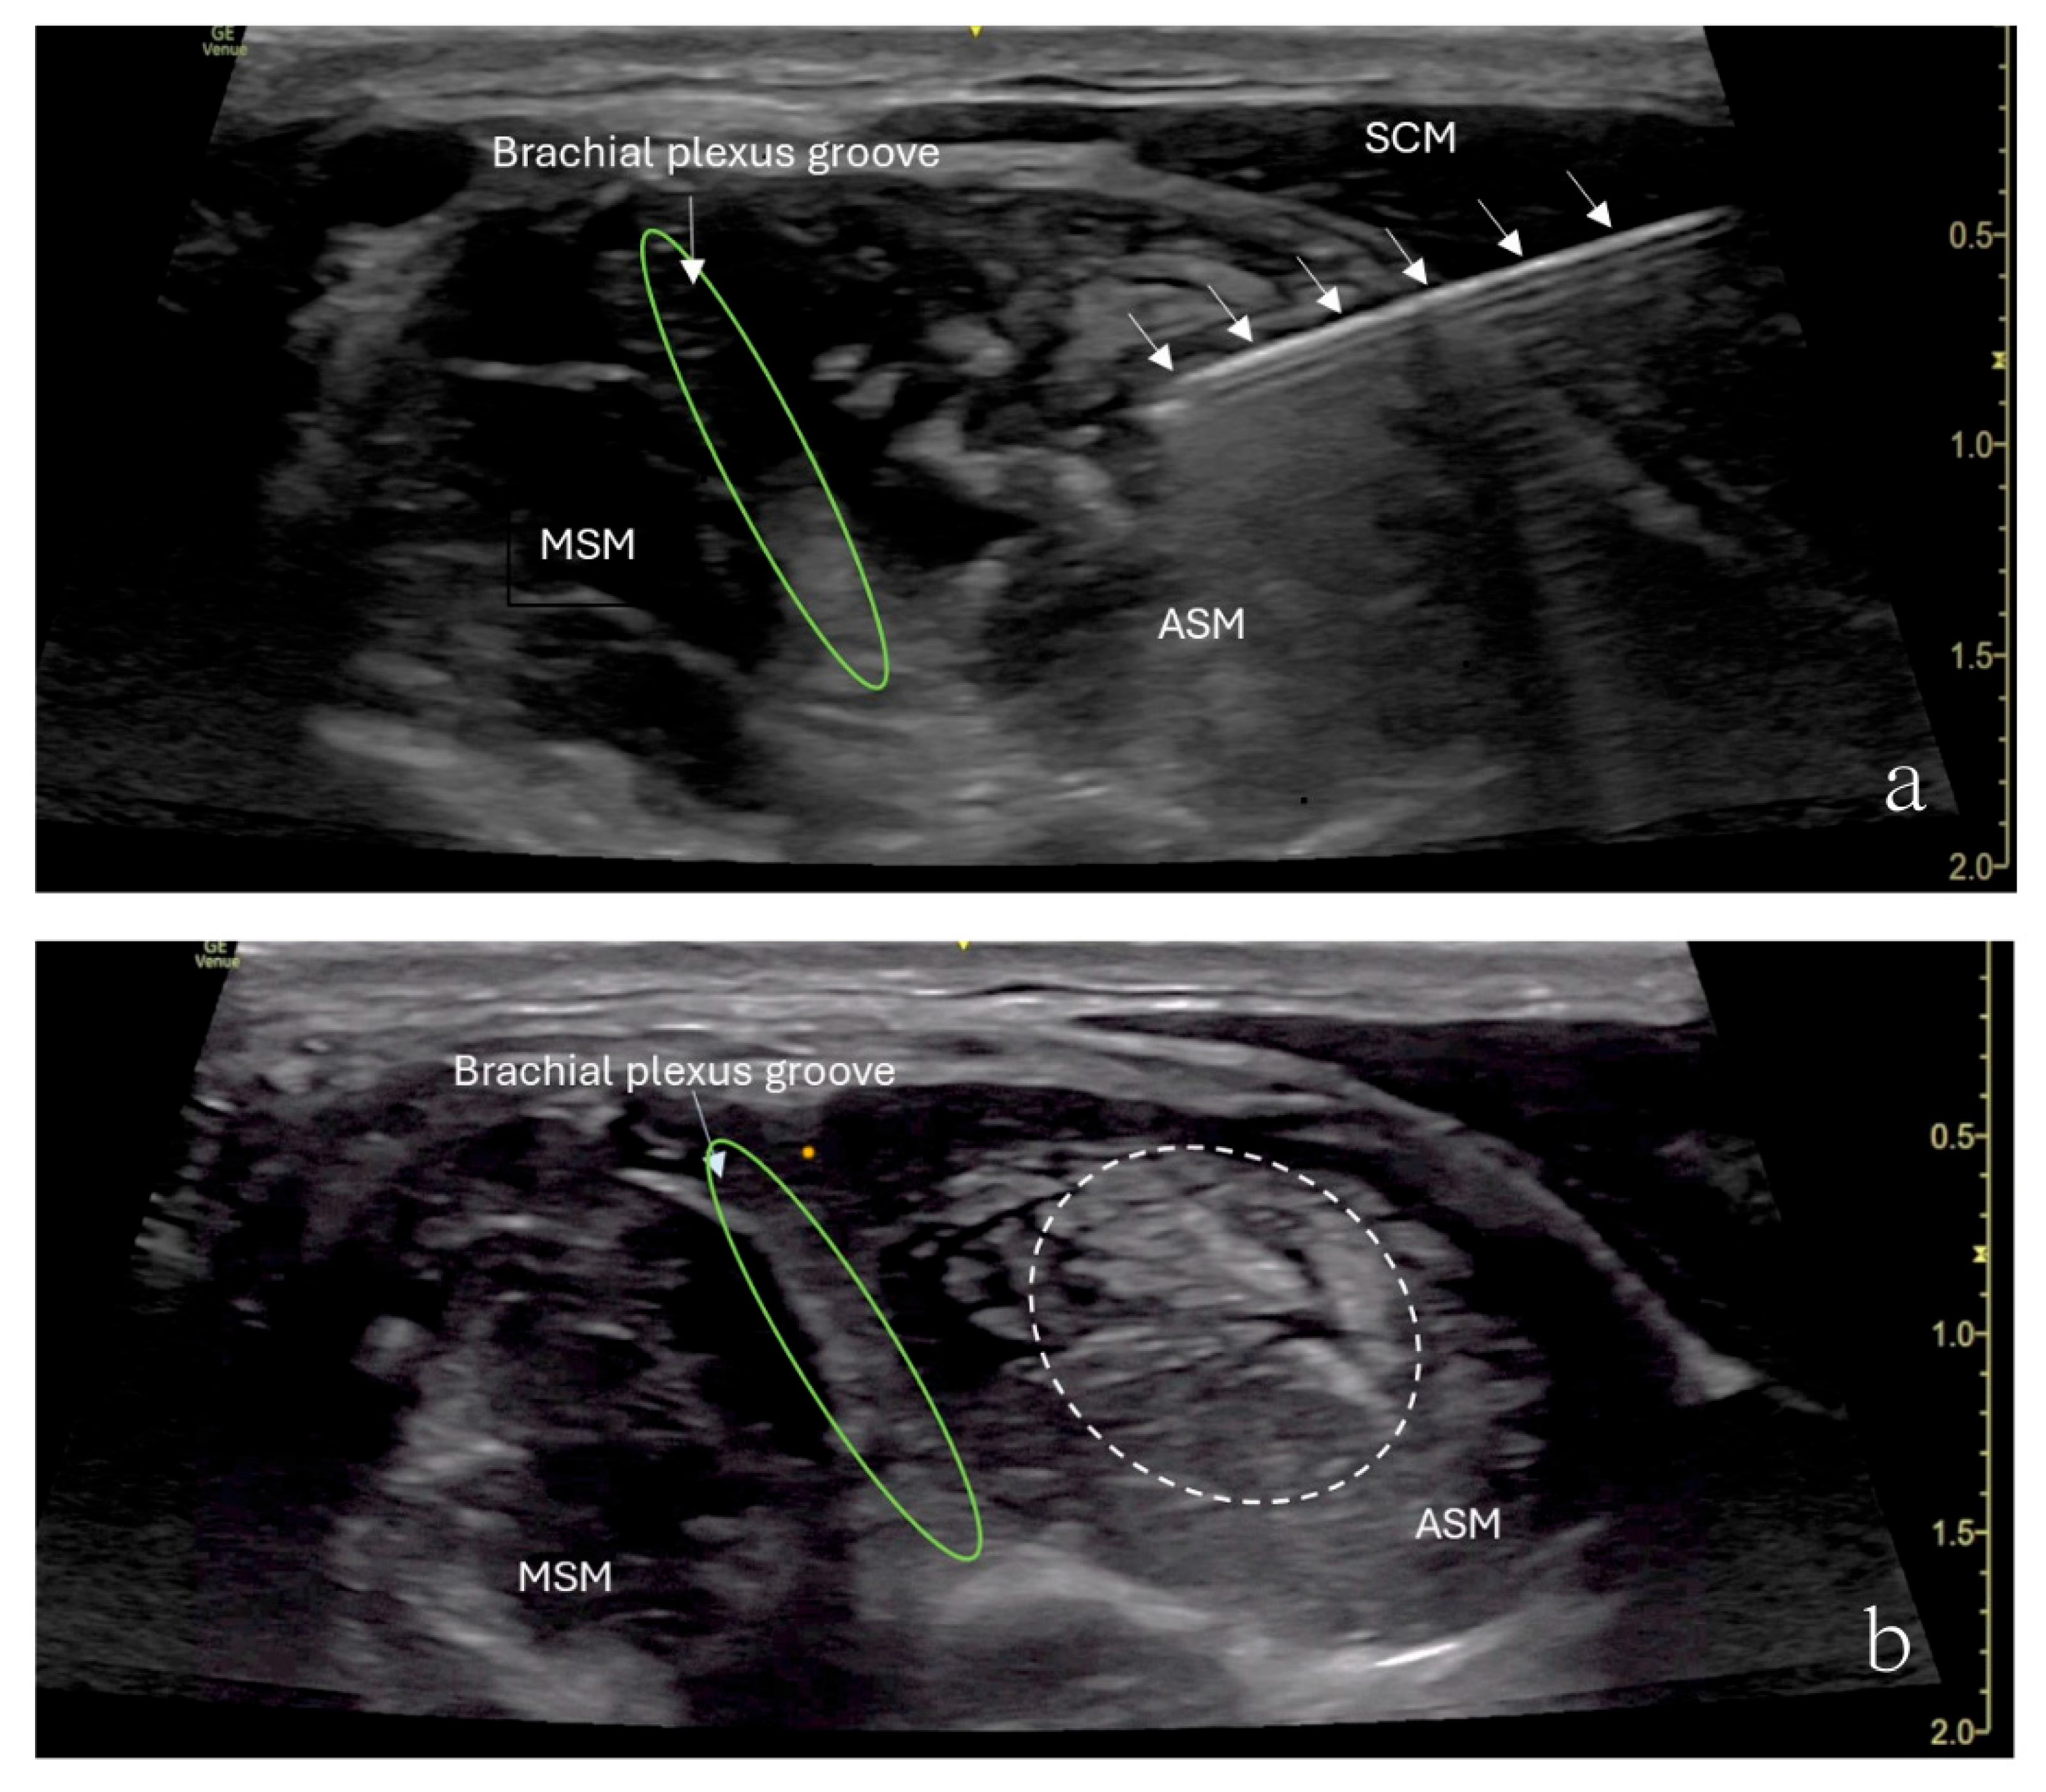

The patient underwent ultrasound-guided ASMB under minimal sedation. A high-frequency linear ultrasound probe was used to identify the anterior scalene muscle and adjacent neurovascular structures. After sterile preparation, a 24-gauge, 40 mm Sono-TAP needle (PAJUNK®, Geisingen, Baden-Württemberg, Germany), using an in-plane approach, was advanced from the anterior aspect of the neck posteriorly and inserted into the middle of the anterior scalene muscle (Figure 2). After negative aspiration, 5 mL of 0.5% ropivacaine was injected incrementally (Figure 2). The block provided immediate pain relief, and there was no numbness in the right upper extremity when the arm was elevated or abducted. However, the patient developed right-sided Horner’s syndrome and experienced weakness in the right shoulder, both of which were resolved shortly after the procedure. Her preexisting symptoms were resolved for approximately 3 h following the block.

Figure 2.

Ultrasound image showing an anterior scalene muscle block in a 15-year-old girl. (a) Needle (arrows) inserted into the anterior scalene muscle (ASM), with the needle tip placed in the middle of the anterior scalene muscle. The needle was advanced from the anterior aspect of the neck posteriorly. (b) Brachial plexus groove (green circle) is in between the ASM and MSM. Injected local anesthetics (dashed circle) and an increased muscle size were noticed.